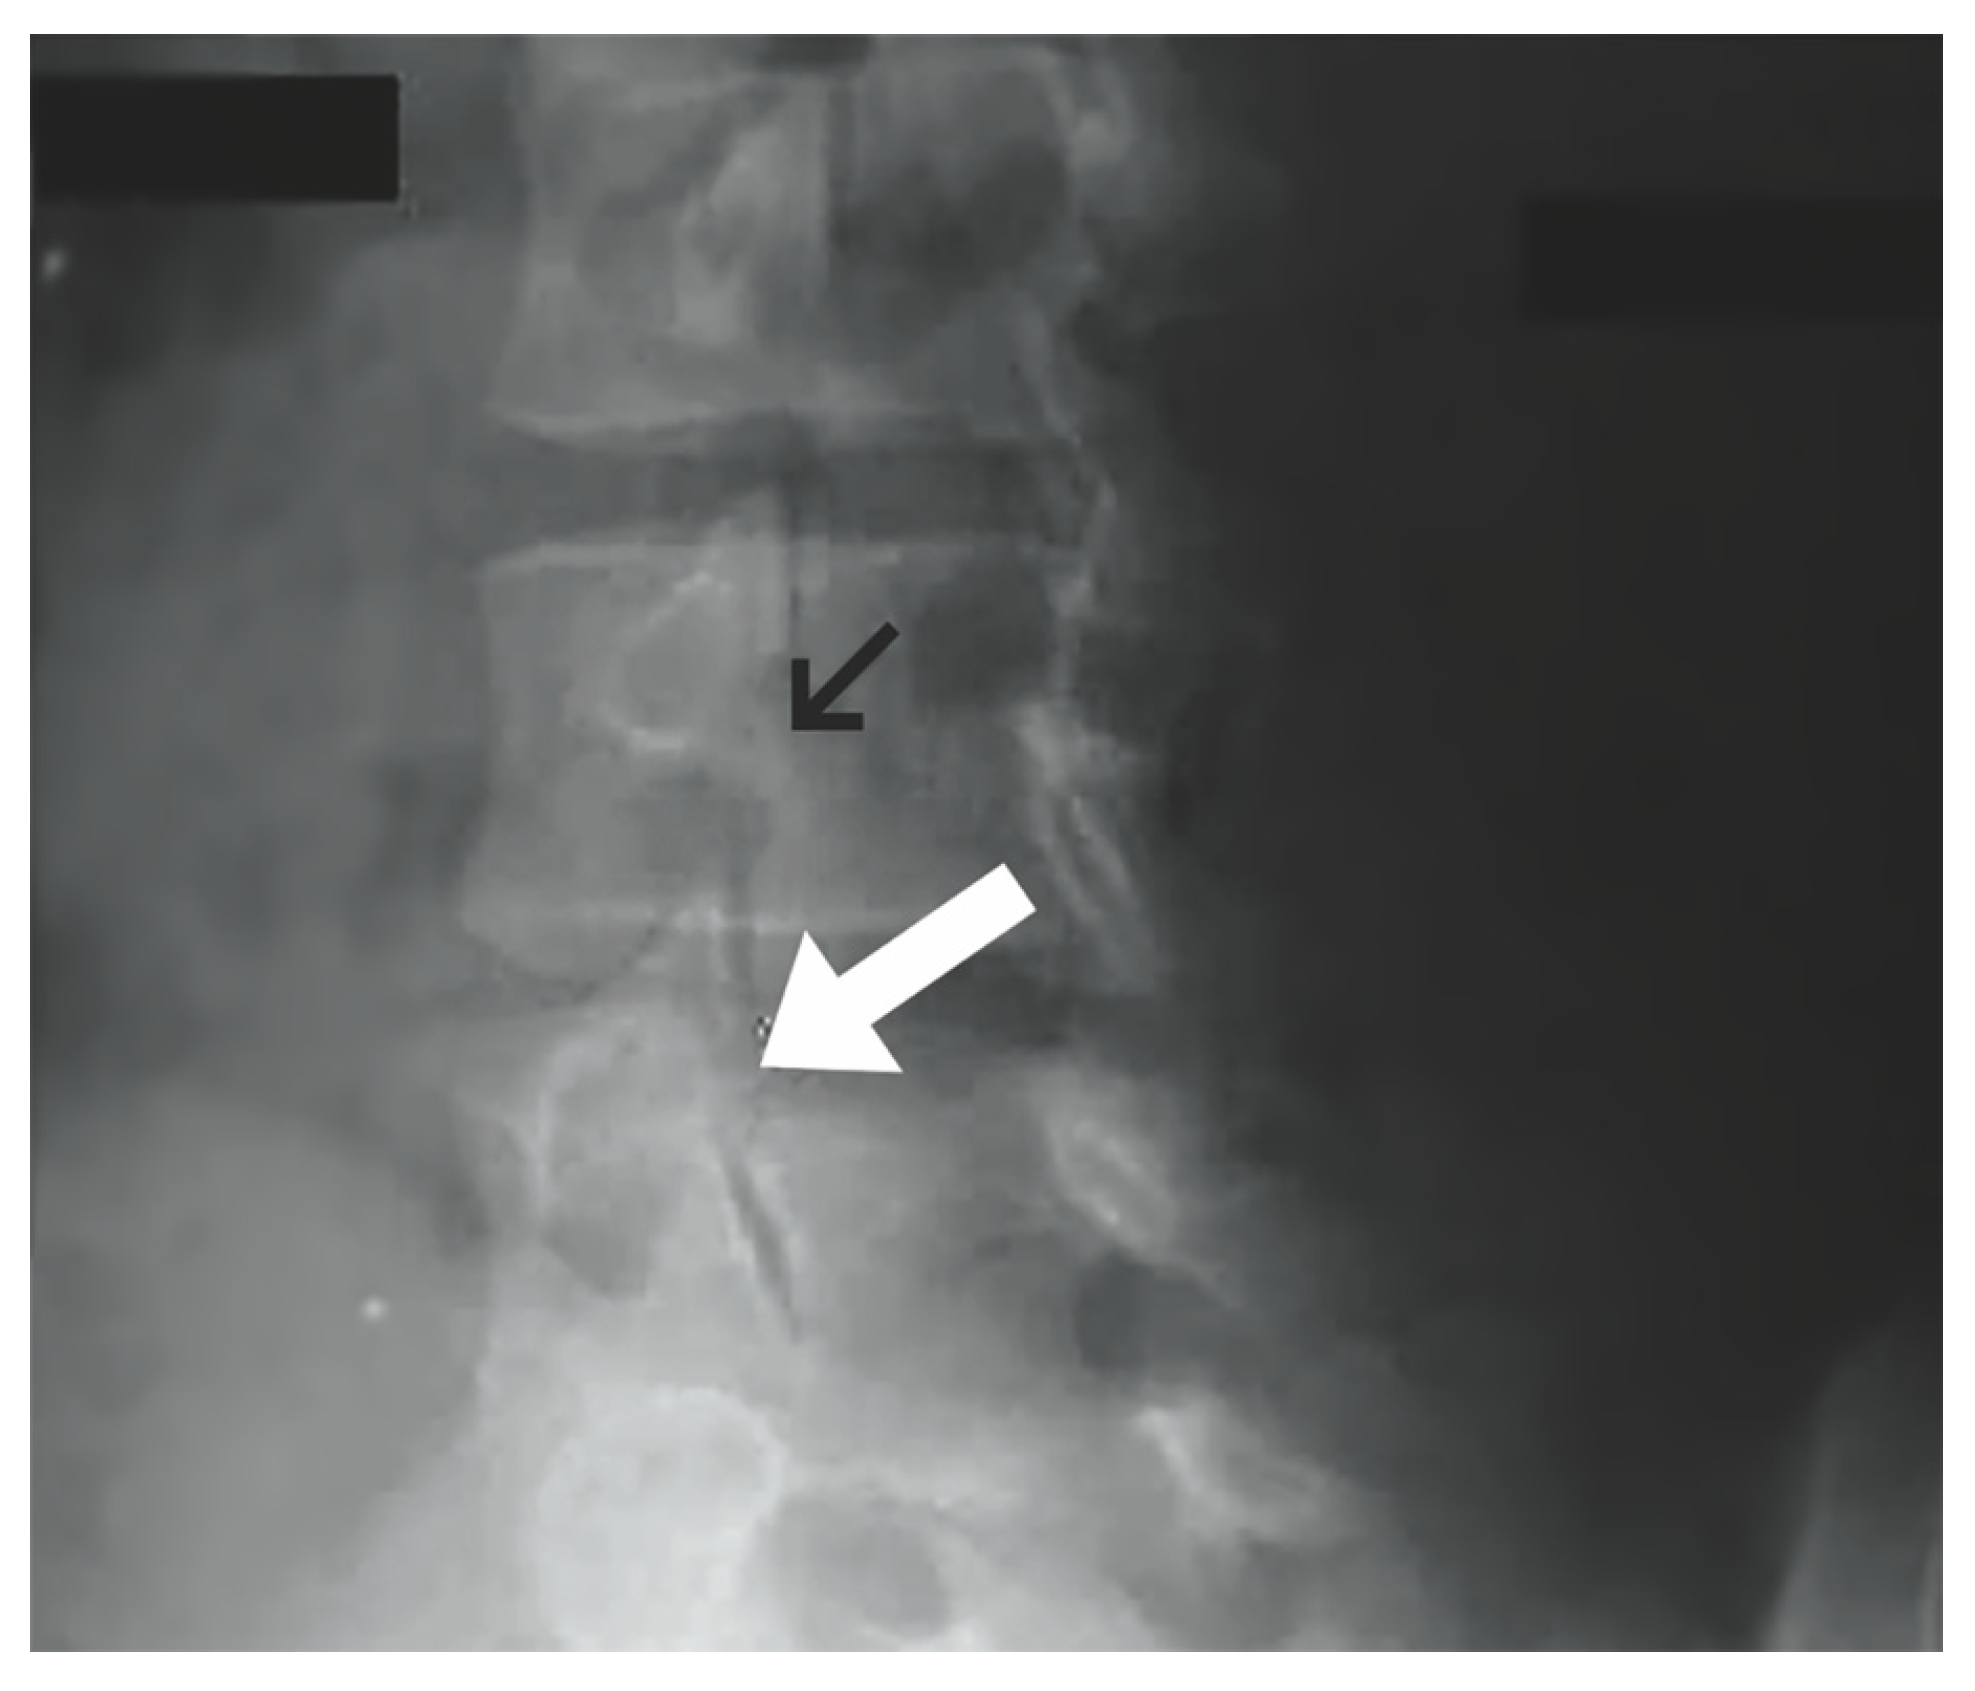

1.9.1. Buck’s Repair

- Buck, J.E. Direct repair of the defect in spondylolisthesis. J. Bone Jt. Surg. Br. Vol. 1970, 52-B, 432–437. [Google Scholar] [CrossRef]

- Li, Y.; Li, H.; Chang, X.; Hu, Z.; Mu, X.; Liu, C.; Gao, X.; Zhang, Y.; Zhou, Y.; Li, C. Retrospective comparative study of pedicle screw fixation via quadrant retractor and buck’s technique in the treatment of adolescent spondylolysis. Orthop. Surg. 2022, 14, 111–118. [Google Scholar] [CrossRef] [PubMed]